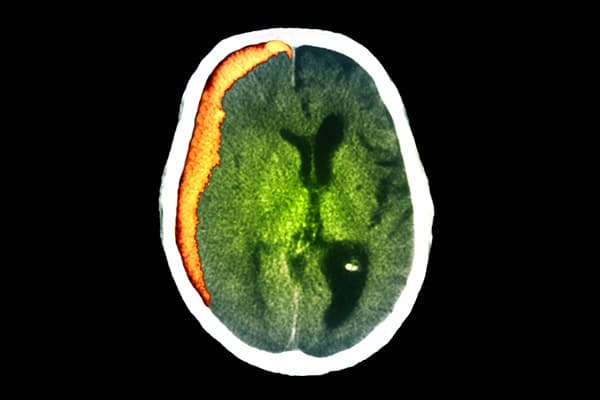

الورم الدموي تحت الجافية

الورم الدموي تحت الجافية: الأسباب والأعراض والتشخيص والعلاج